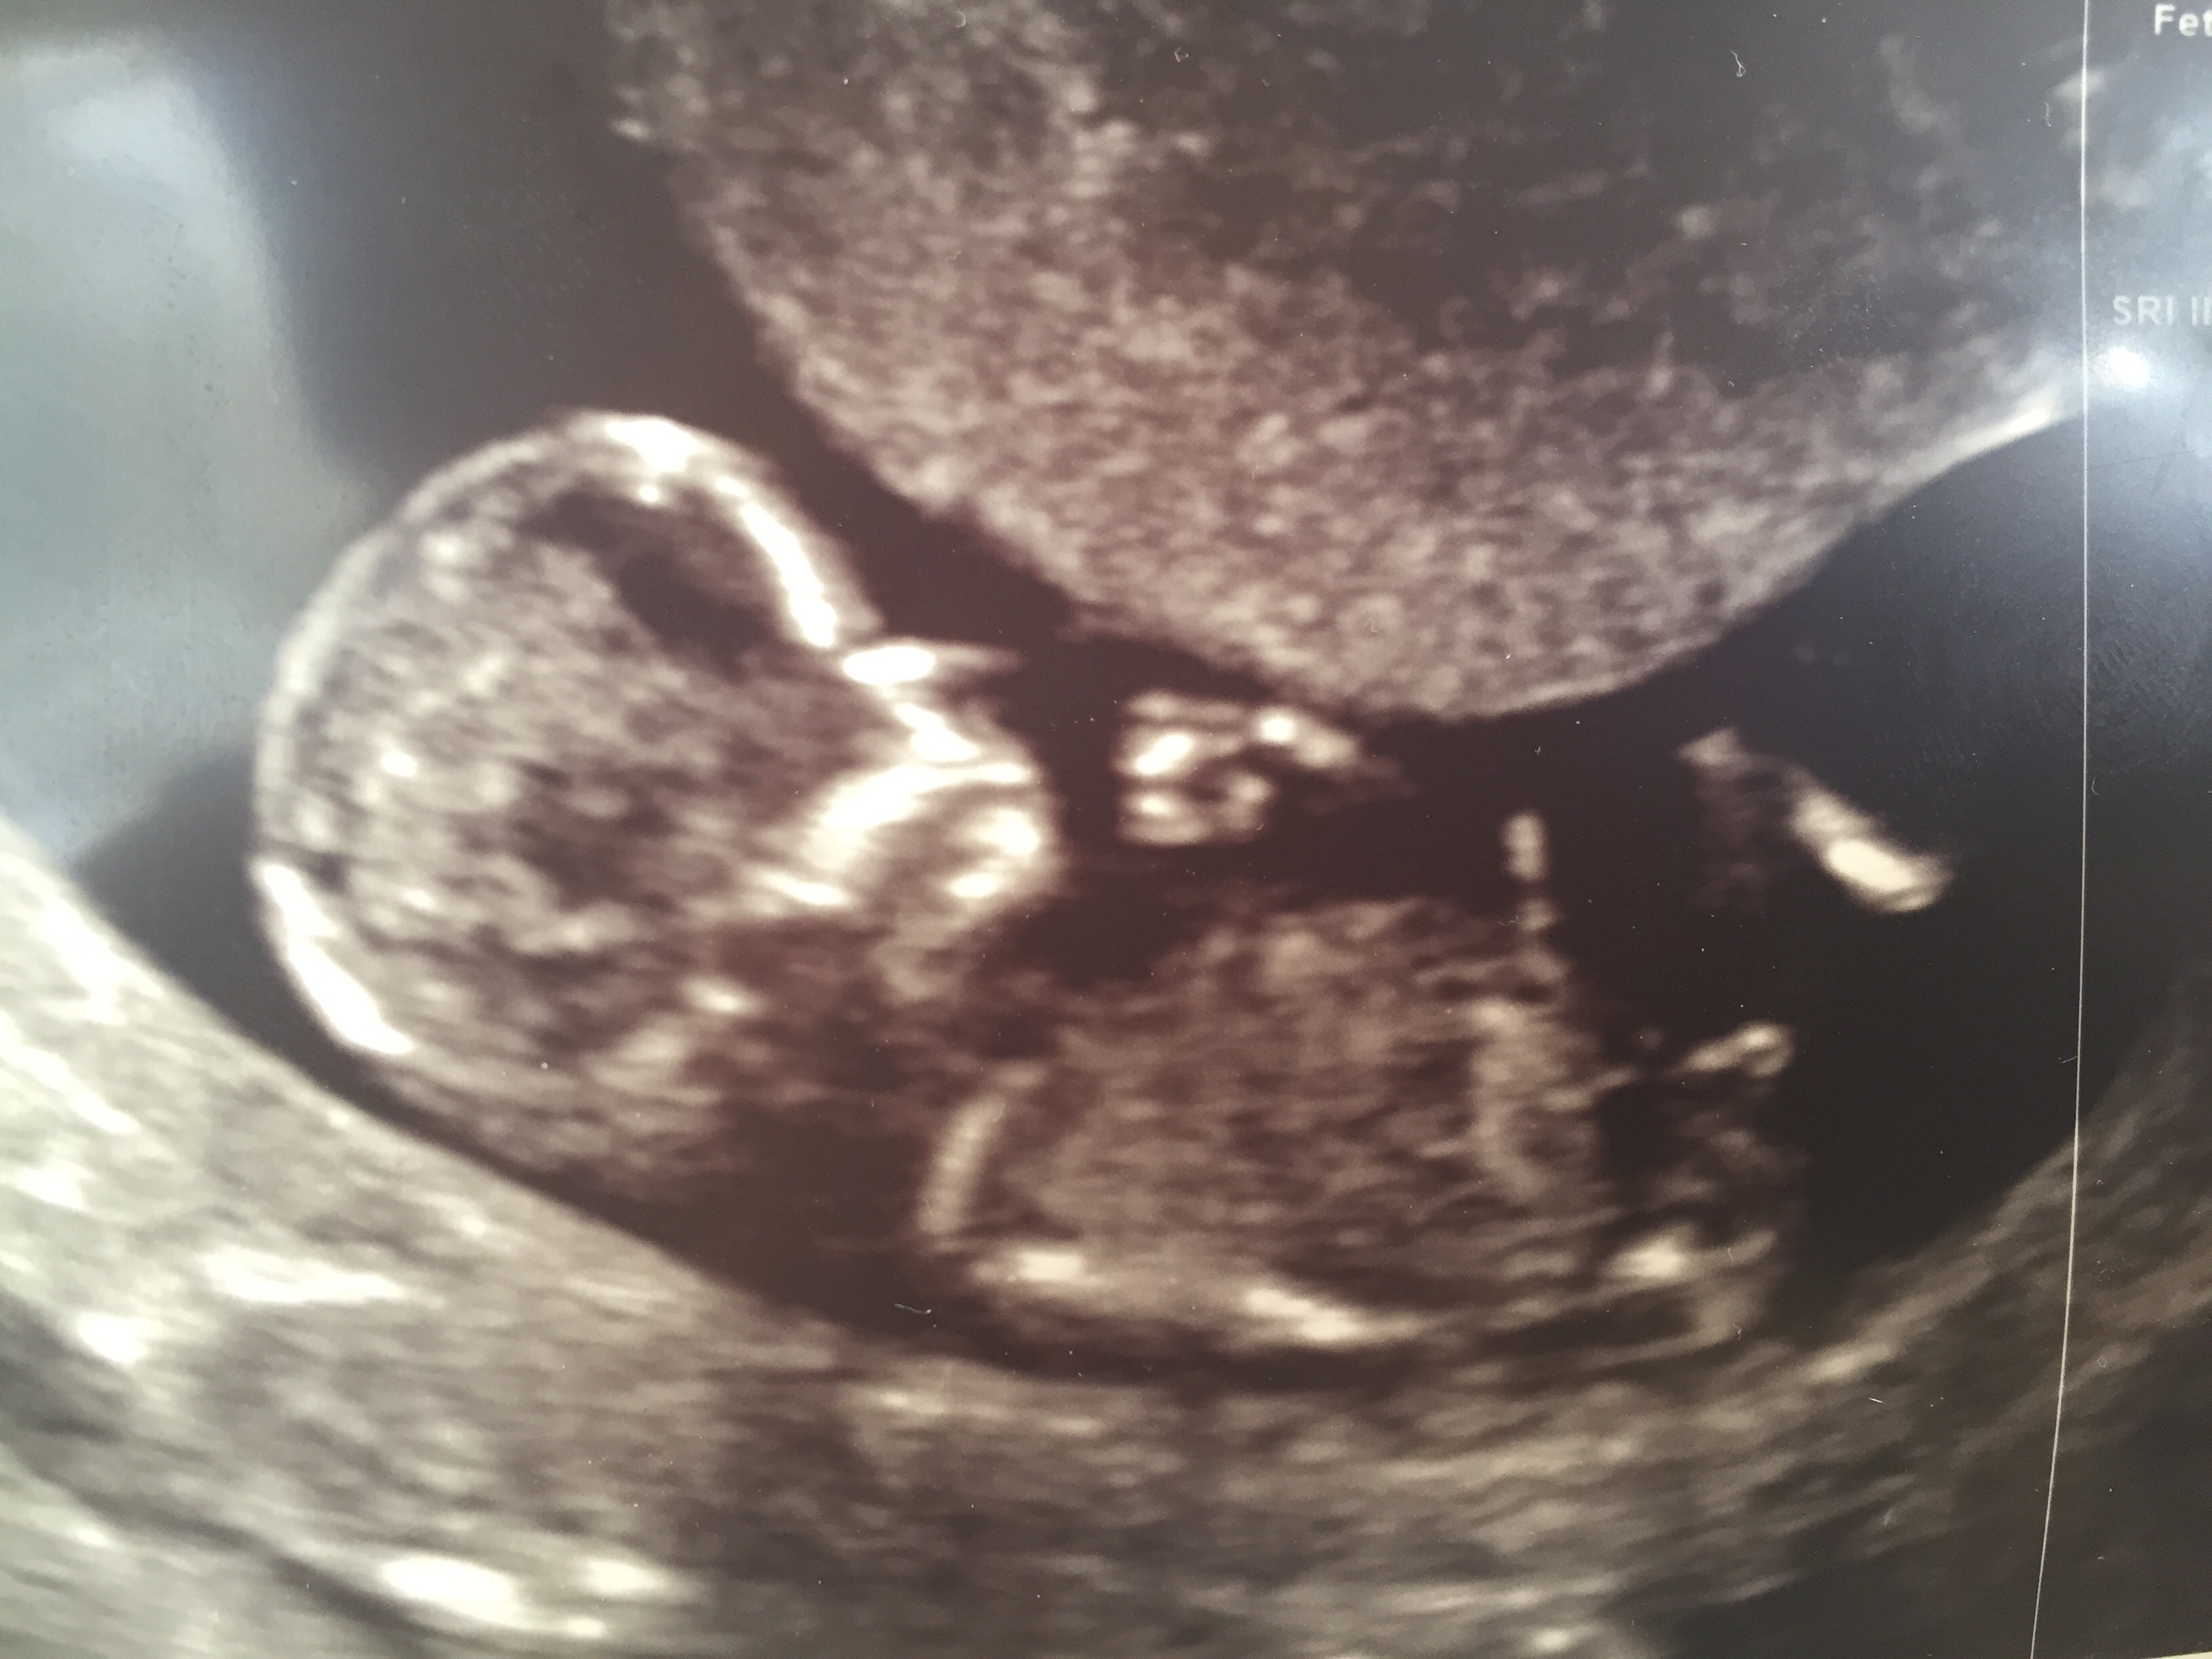

What do you think ???? Its a 12w 4 d scan.

boy nub and skull

This is a super boy nub!